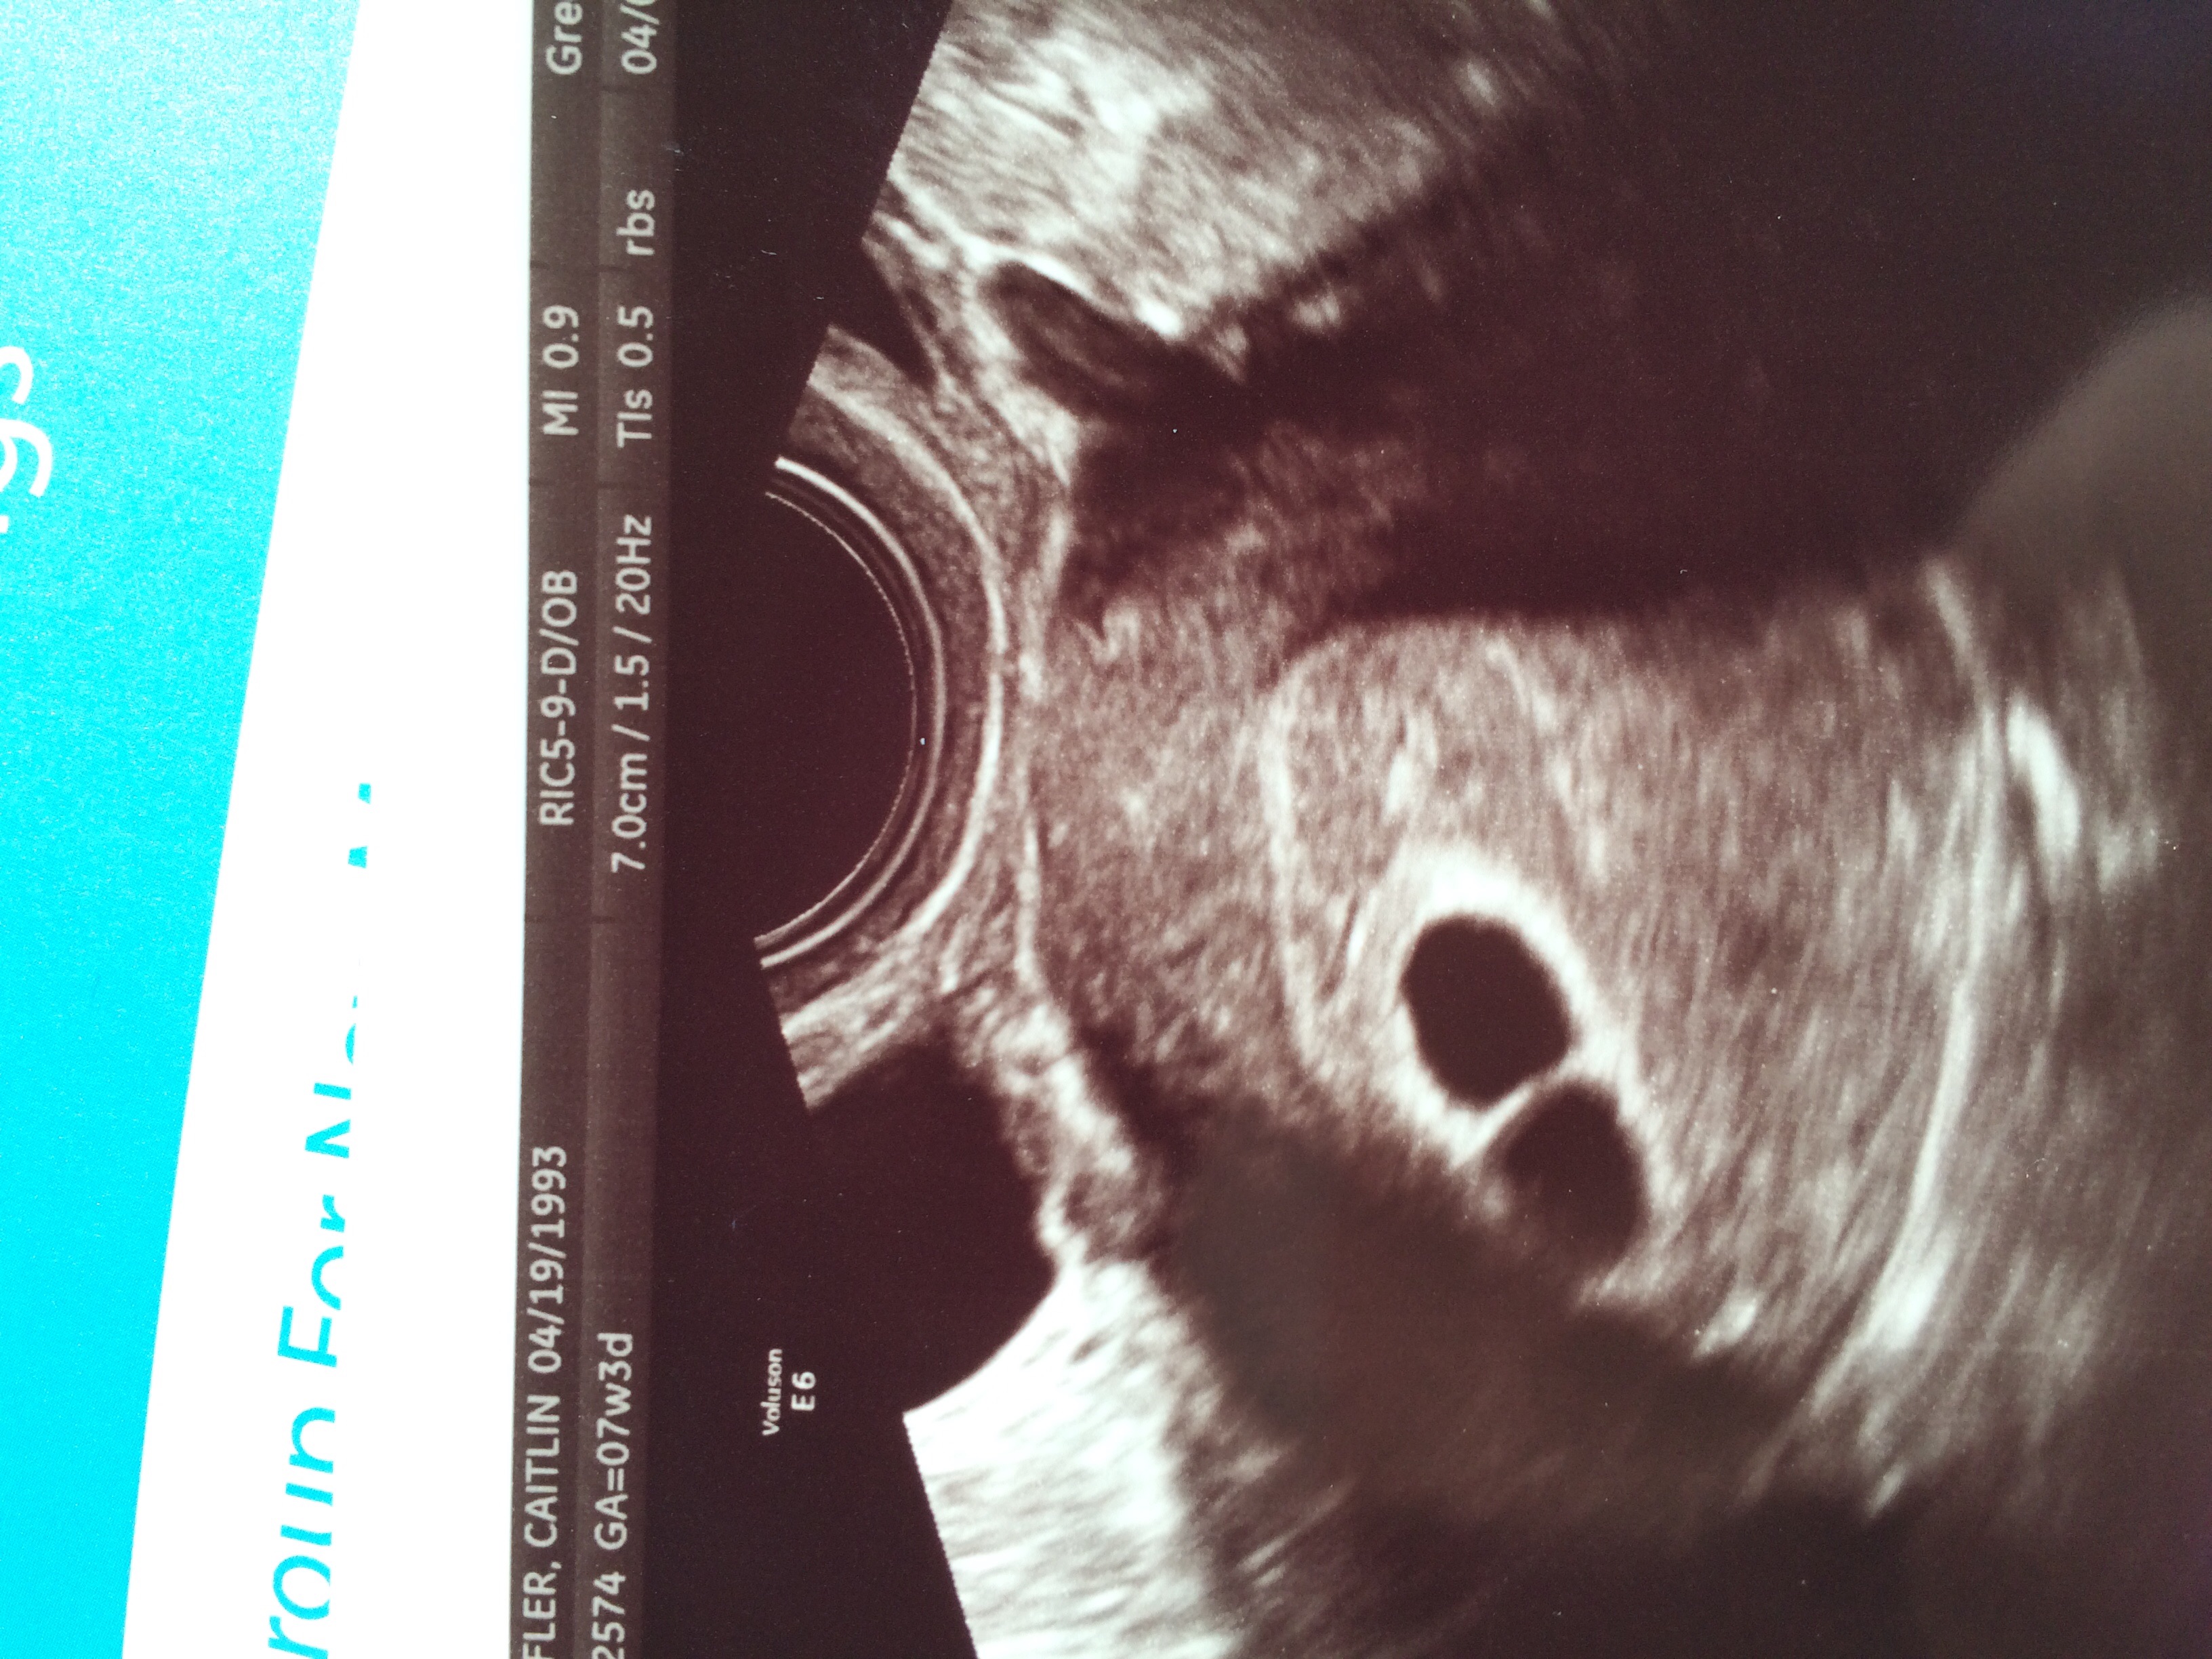

Personally it started as a confirmation ultrasound being done at a local "pregnancy center"; they do confirming ultrasounds for free and if need be work with you through your pregnancy. The results of that ultrasound raised a concern and I contacted my midwife who ordered blood work and a viability/dating ultrasound be done at the hospital. After the results of that which I posted above they have scheduled a follow up ultrasound in a few weeks to confirm viability again due to how early i am.